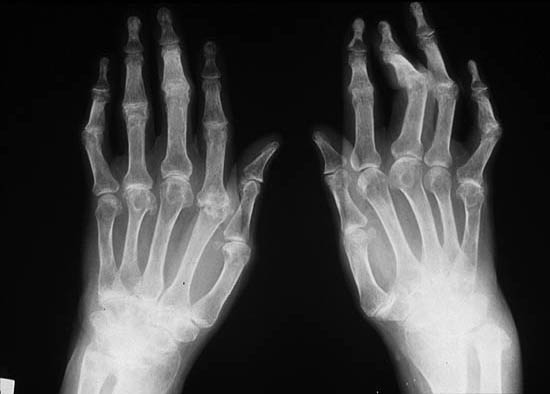

La Traumatología y Ortopedia, es una especialidad de la medicina, dedicada específicamente a las enfermedades del sistema musculo-esquelético.

Enfermedades reumáticas

• Artritis